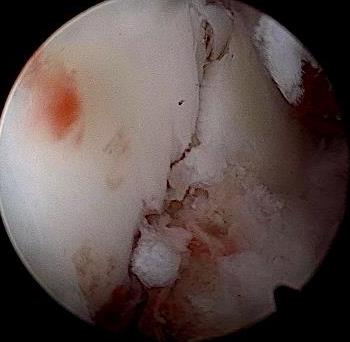

• 关节镜技术联合钉中钉系统全内修复跟骨关节内骨折的临床疗效观察

摘要:目的 探讨关节镜技术联合钉中钉系统全内修复跟骨关节内骨折的临床疗效。方法 回顾性分析2021年5月-2024年4月该院骨与关节康复科收治,并获得随访的31例闭合性跟骨关节内骨折患者的临床资料。均采取关节镜技术联合钉中钉系统全内修复手术治疗方案。术前及术后均行跟骨侧轴位X线片及足部CT检查,根据影像学结果对骨折类型进行分型,并评价术后骨折复位情况。比较手术前后跟骨高度、宽度、Bohler角和Gissane角。记录术前等待时间、手术时间、术中出血量、住院时间、术后疼痛视觉模拟评分法(VAS)评分等围手术期相关指标及术后并发症发生情况。采用美国足踝外科协会(AOFAS)评分和Maryland足部评分评估临床疗效。结果 术后影像学检查,可见跟骨术后关节面塌陷骨块复位;跟骨高度明显高于术前,跟骨宽度明显窄于术前,Bohler角较术前明显增大,Gissane角较术前明显缩小,差异均有统计学意义(P < 0.05)。术前等待时间为6(4,7)d,手术时间为(188.77±39.53)min,术中出血量为(59.03±23.00)mL,住院时间为(16.49±4.04)d,术后疼痛VAS评分为2(1,2)分,AOFAS评分为92(90,95)分,Maryland评分为92(90,95)分。结论 采用关节镜技术联合钉中钉系统全内修复跟骨骨折,具有可早期开展手术、创伤小、直视下复位、固定可靠和无切口相关并发症等优点,适用于Sanders Ⅱ型和Ⅲ型跟骨骨折。值得应用于临床。